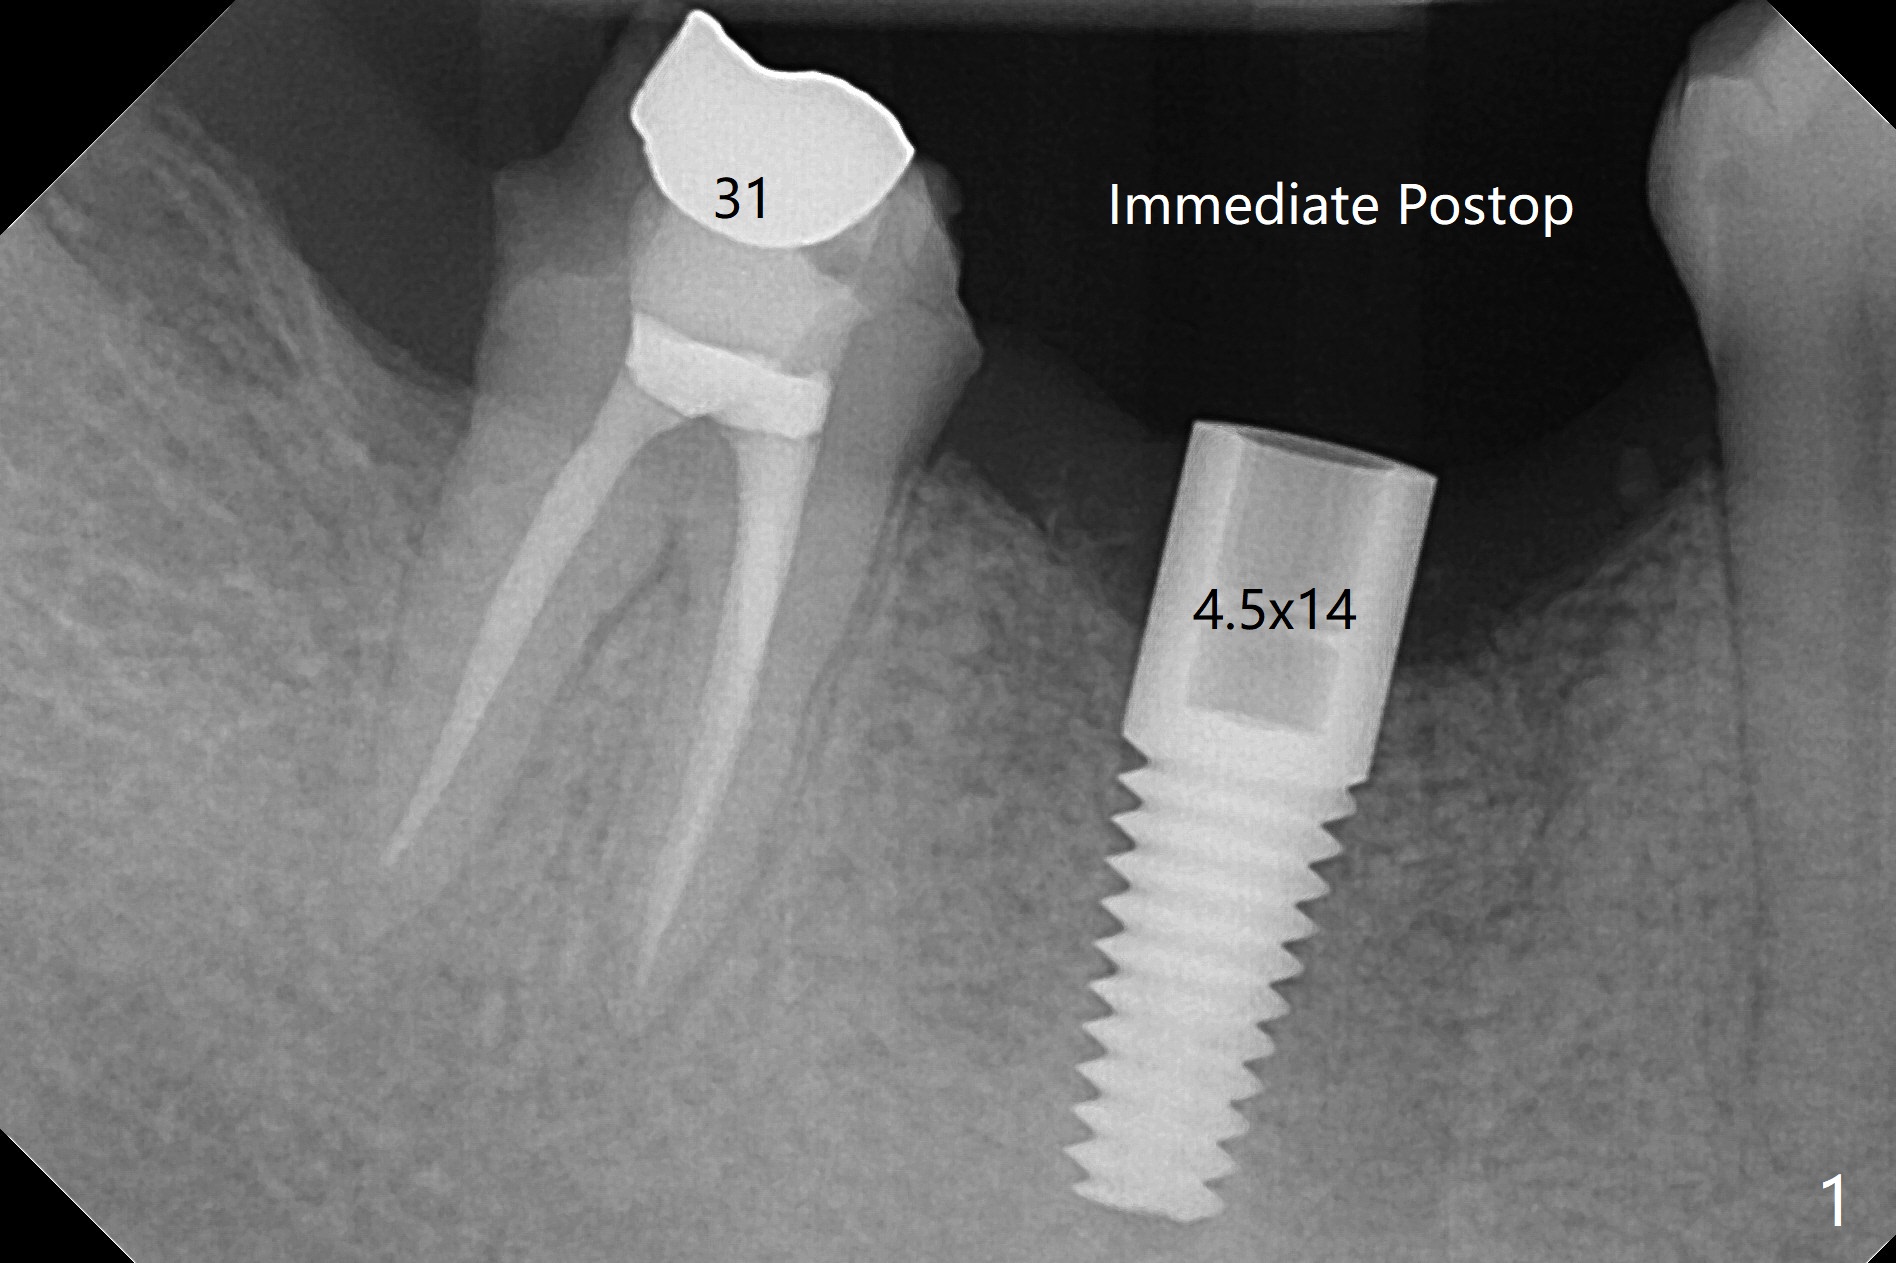

右下第一磨牙植体取出,植骨5.5月后,植牙区颊侧角化龈多,使用环形刀开始导板钻洞,最后徒手种植(图一),美中不足植体植体舌侧粗糙面暴露,一直到术后三周(图二,三),而且接近非角化龈(N;(K: 角化龈)),这可能与舌侧牙槽嵴斜坡比较陡有关,如果术前注意到这一点,术中又使用环形刀定位,切开导板种植,问题便可以避免。准备术后3个月拍摄CT,证实舌侧螺纹是否裸露。如果不明显,使用愈合袖(healing cuff),方便取模。